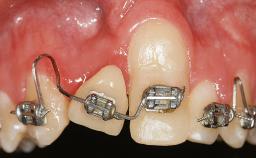

GBR and Soft-Tissue Augmentation Following Explantation to Rehabilitate a Soft- and Hard-Tissue Defect

It is sometimes necessary to remove and replace compromised implants. This case is a clear example of the need for multiple steps to achieve an optimal therapeutic result for patients with non-salvageable implants. It illustrates how the lost soft and hard tissues were rebuilt in a sequence that improved the healing of the hard tissues and assured their long-term stability. The 35-year-old healthy patient presented with clinical attachment loss on the proximal and lingual surfaces of the natural dentition. Some gingival recession was present on natural teeth, particularly in the posterior sextants (S1, S3, S4, and S6).